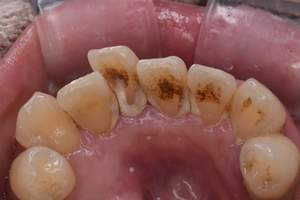

PMTC

治療前

治療後

| 年齢 | 34歳・女性 |

|---|---|

| 主訴 | 着色をとりたい |

| 治療内容 | PMTC |

| 治療期間 | 60分 |

| 費用 | PMTC 5,500円(自費診療) |

| リスク・副作用 | ・生活習慣(喫煙・コーヒーなど)により再度着色することがあります ・PMTCは歯を白くするものではなく着色・バイオフィルムの除去を目的としています ・保険適用外の施術です |